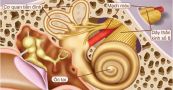

U dây thần kinh thính giác là một căn bệnh phổ biến. Tuy là u lành tính nhưng có thể ảnh hưởng đến một trong hai tai hoặc cả hai tai. Tìm hiểu ngay bài viết dưới đây để hiểu rõ hơn về bệnh lý này.